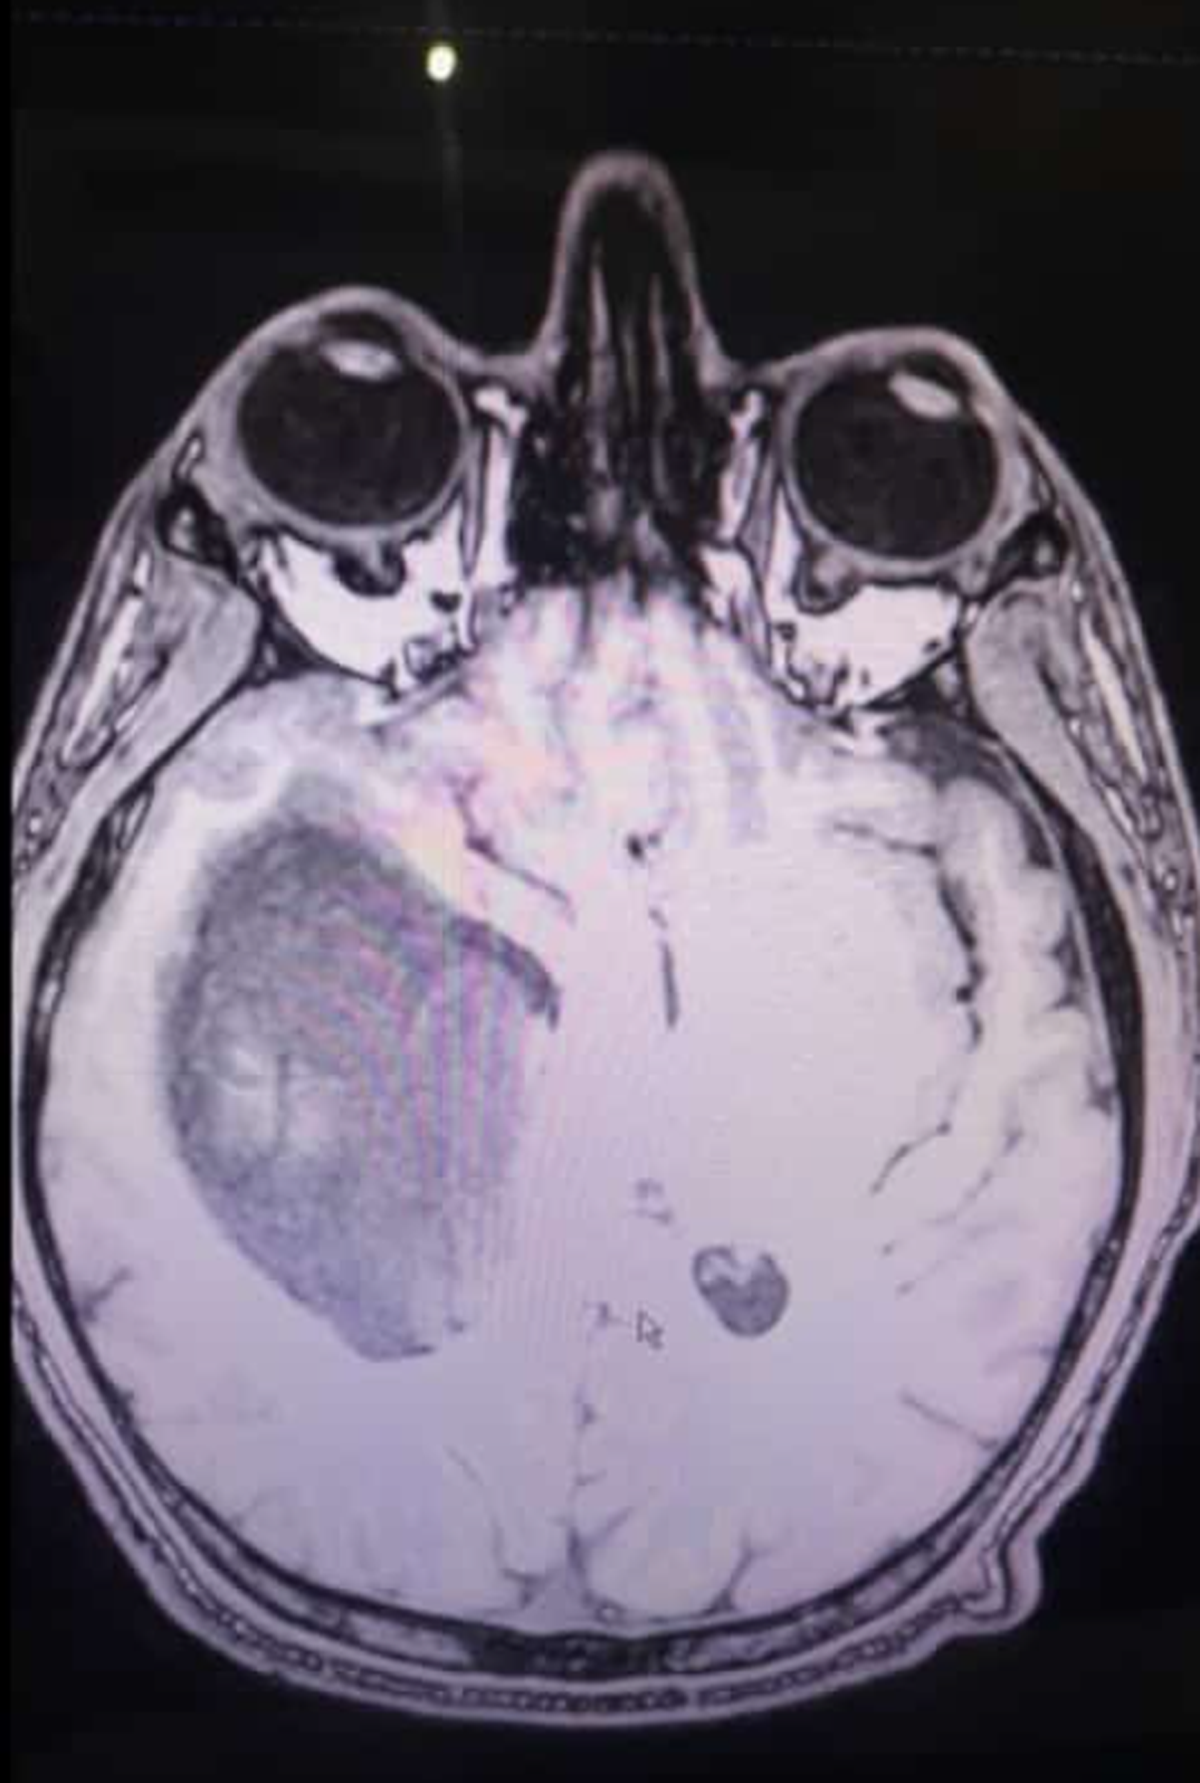

Isaías tiene 34 años. Descubrieron que tenía un tumor de 12 centímetros y le dijeron que le quedaba poco tiempo de vida. "Es un milagro en pie", aseguran.

"El doctor le dijo que ya no había tumor, pero a los dos años, en el último control, se vio en las imágenes que había aparecido un nuevo tumor que creció 12 centímetros en seis meses", recordó Silvina. Y continuó: "Este era un tumor más grande, más agresivo y con una ubicación que hacía imposible su operación, excepto en una clínica en Latinoamérica que contaba con aparatos de alta precisión".